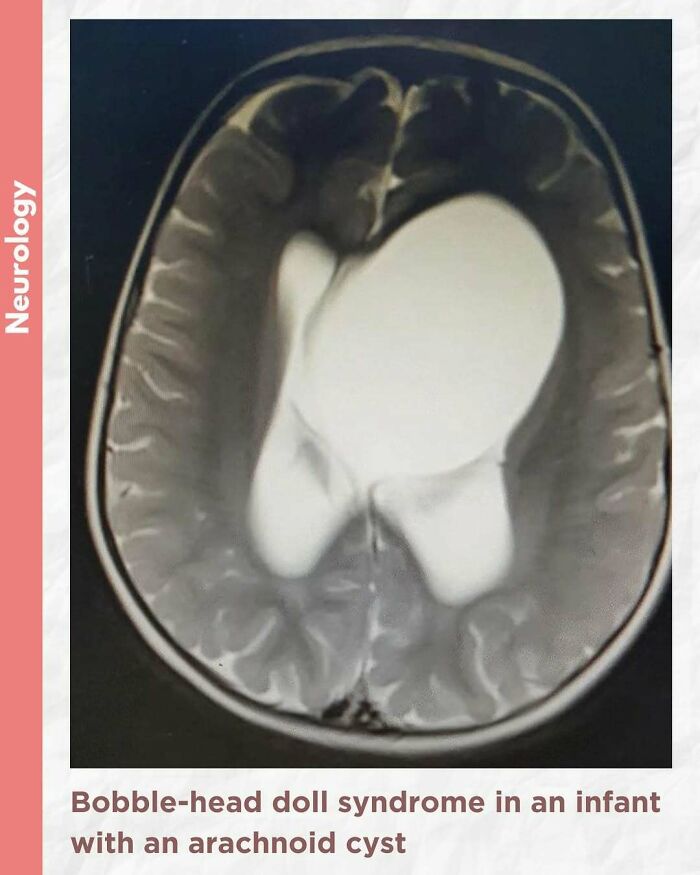

Bobble-head doll syndrome in an infant with an arachnoid cyst

Bobble-head doll syndrome is a rare neurological movement disorder in which patients, usually children around age 3, begin to bob their head and shoulders forward and back, or sometimes side-to-side, involuntarily, in a manner reminiscent of a bobble head doll. The syndrome is related to cystic lesions and swelling of the third ventricle in the brain. Symptoms of bobble-head doll syndrome are diverse but can be grouped into two categories: physical and neurological. The most common form of treatment is surgical implanting of a shunt to relieve the swelling of the brain.

A 1.5-year-old girl presented to the pediatric clinic with the chief complaints of gradual onset excessive head nodding (side-to-side movement) for 3 months. Movements increased with walking, emotions, and stress; decreased during periods of concentration; and were absent during sleep. There were no other complaints or headaches. There was no other significant history.

The child was alert, with normal cognitive function. Neurological examination was normal. Initial laboratory assessment including CBC, hepatic and renal function, and endocrine function tests were normal.

Cranial MRI demonstrated a large left-hemispheric cystic process with a midline shift, well-defined thin-walled suprasellar arachnoid cyst measuring 3 × 5 × 7 cm that obstructed the foramina of Monro, with resulting hydrocephalus ventriculomegaly. Based on the cranial MRI and symptoms, a diagnosis of a suprasellar arachnoid cyst with BHDS was made. The patient underwent endoscopic cystoventriculostomy and cystocisternostomy for the suprasellar arachnoid cyst. During the 6 months of follow-up, the head bobbing disappeared completely, and her growth was normal.

Despite the rareness of bobble-head doll syndrome, it is considered an important condition that must be investigated early to detect the cause and treated promptly to avoid potential complications.